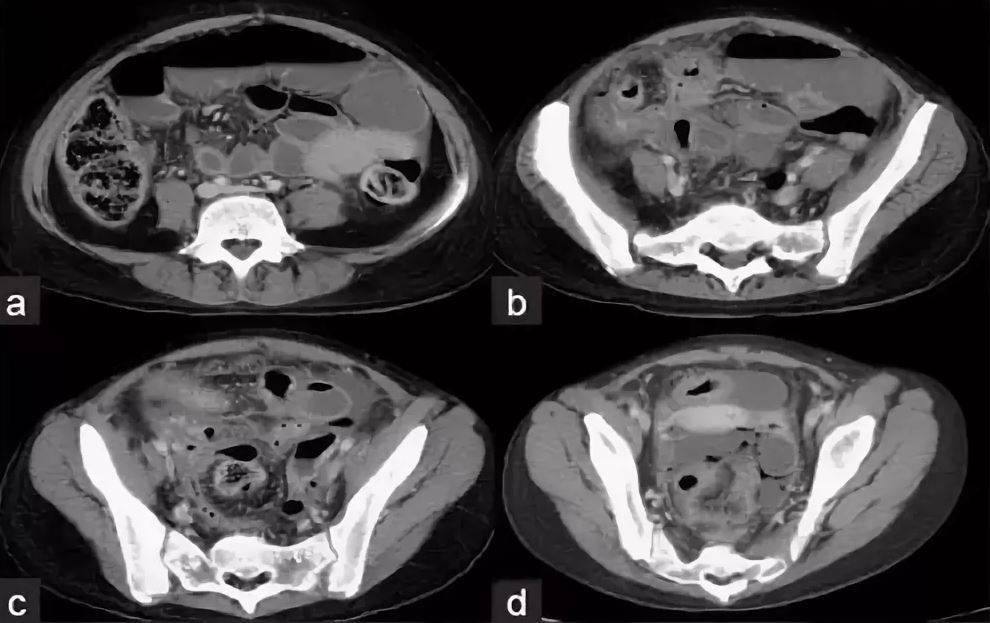

Компьютерная томография органов малого таза: оборудование и результаты исследований

Раздел: Галерея прозрений